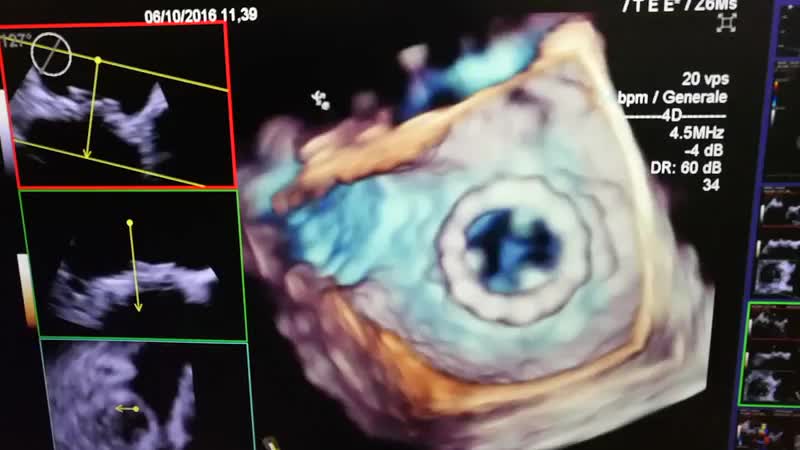

Ascesso perianulare e distacco di protesi aortica meccanicaAutore: Chiara Bencini

Categoria: Videoalbum

Parole chiave: color diagnosi ecotee endocardite protesi -